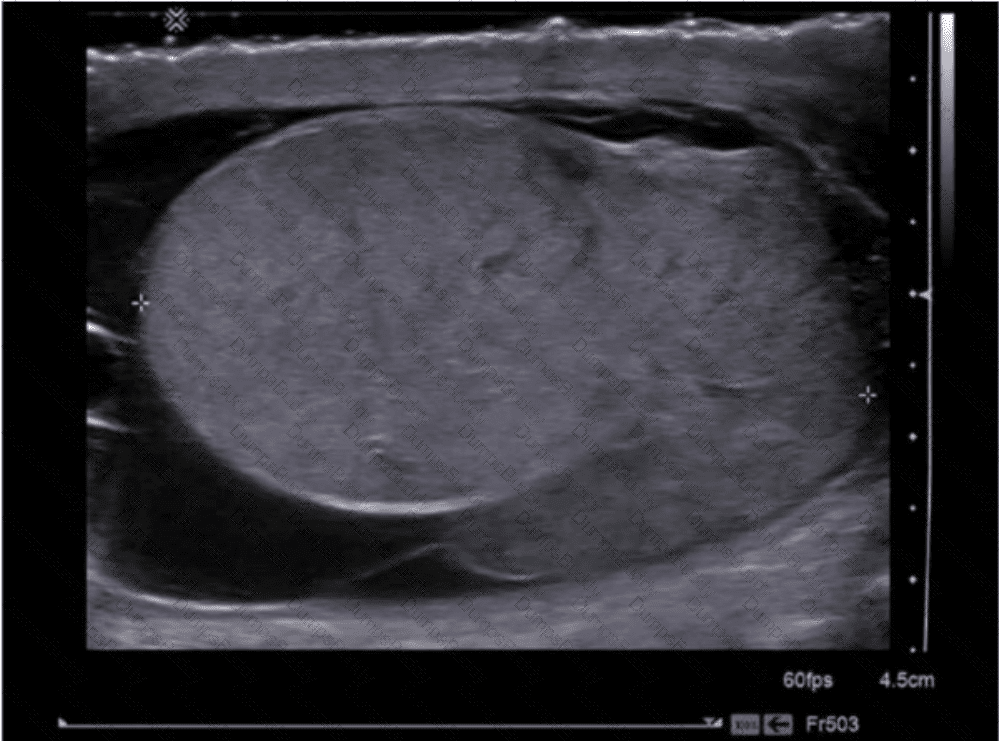

Which diagnosis is most consistent with this image from a patient with acute scrotal pain?